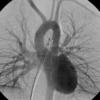

PA angio

Fig 2